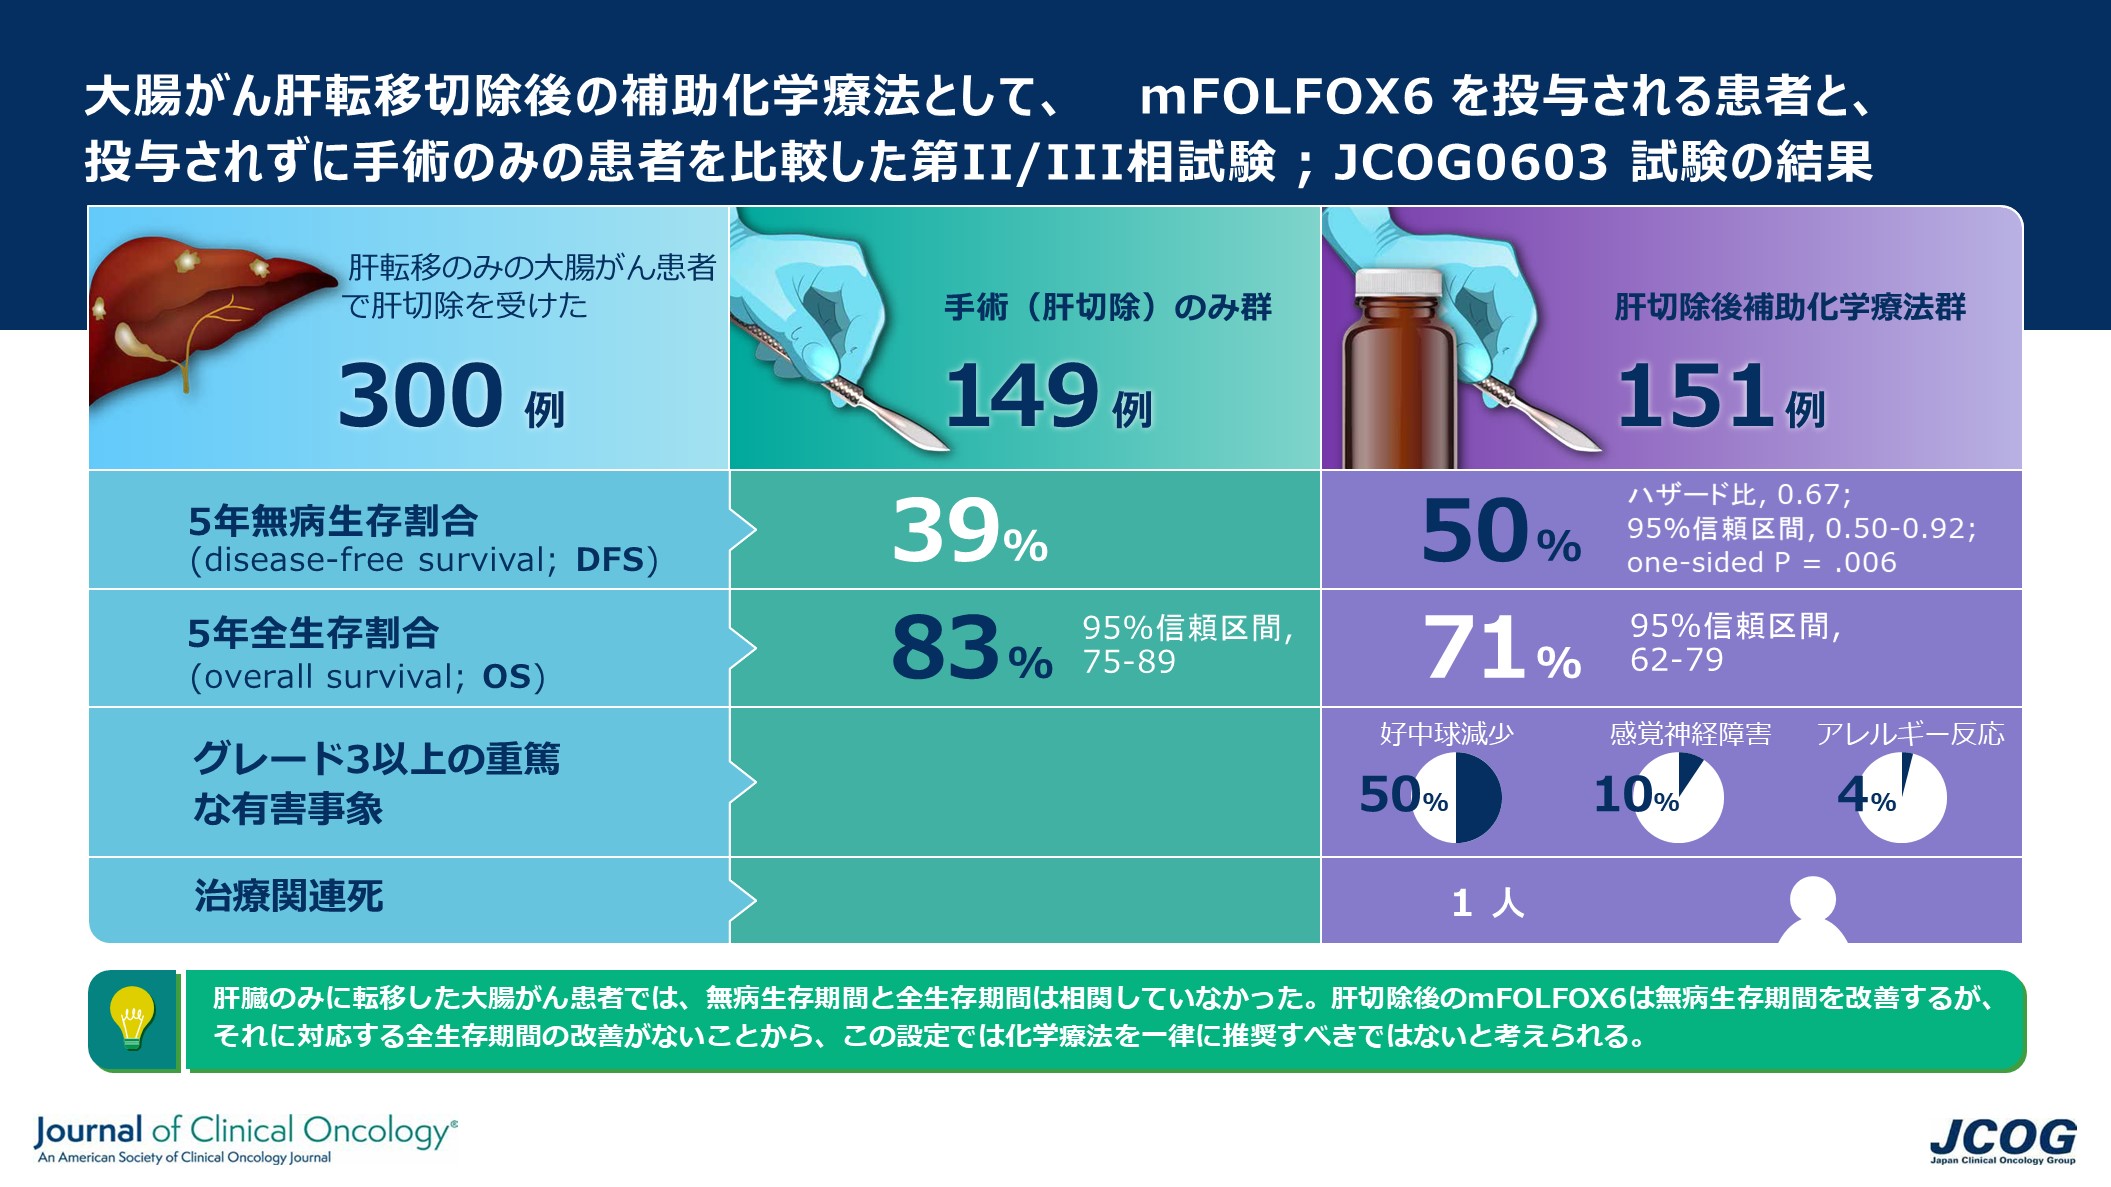

大腸がんの肝転移による肝切除後の新たな標準治療を検証

大腸がんの肝臓への転移に対する肝臓切除後の術後補助化学療法について、切除単独療法よりも優れた治療法であるかどうかを検証し...